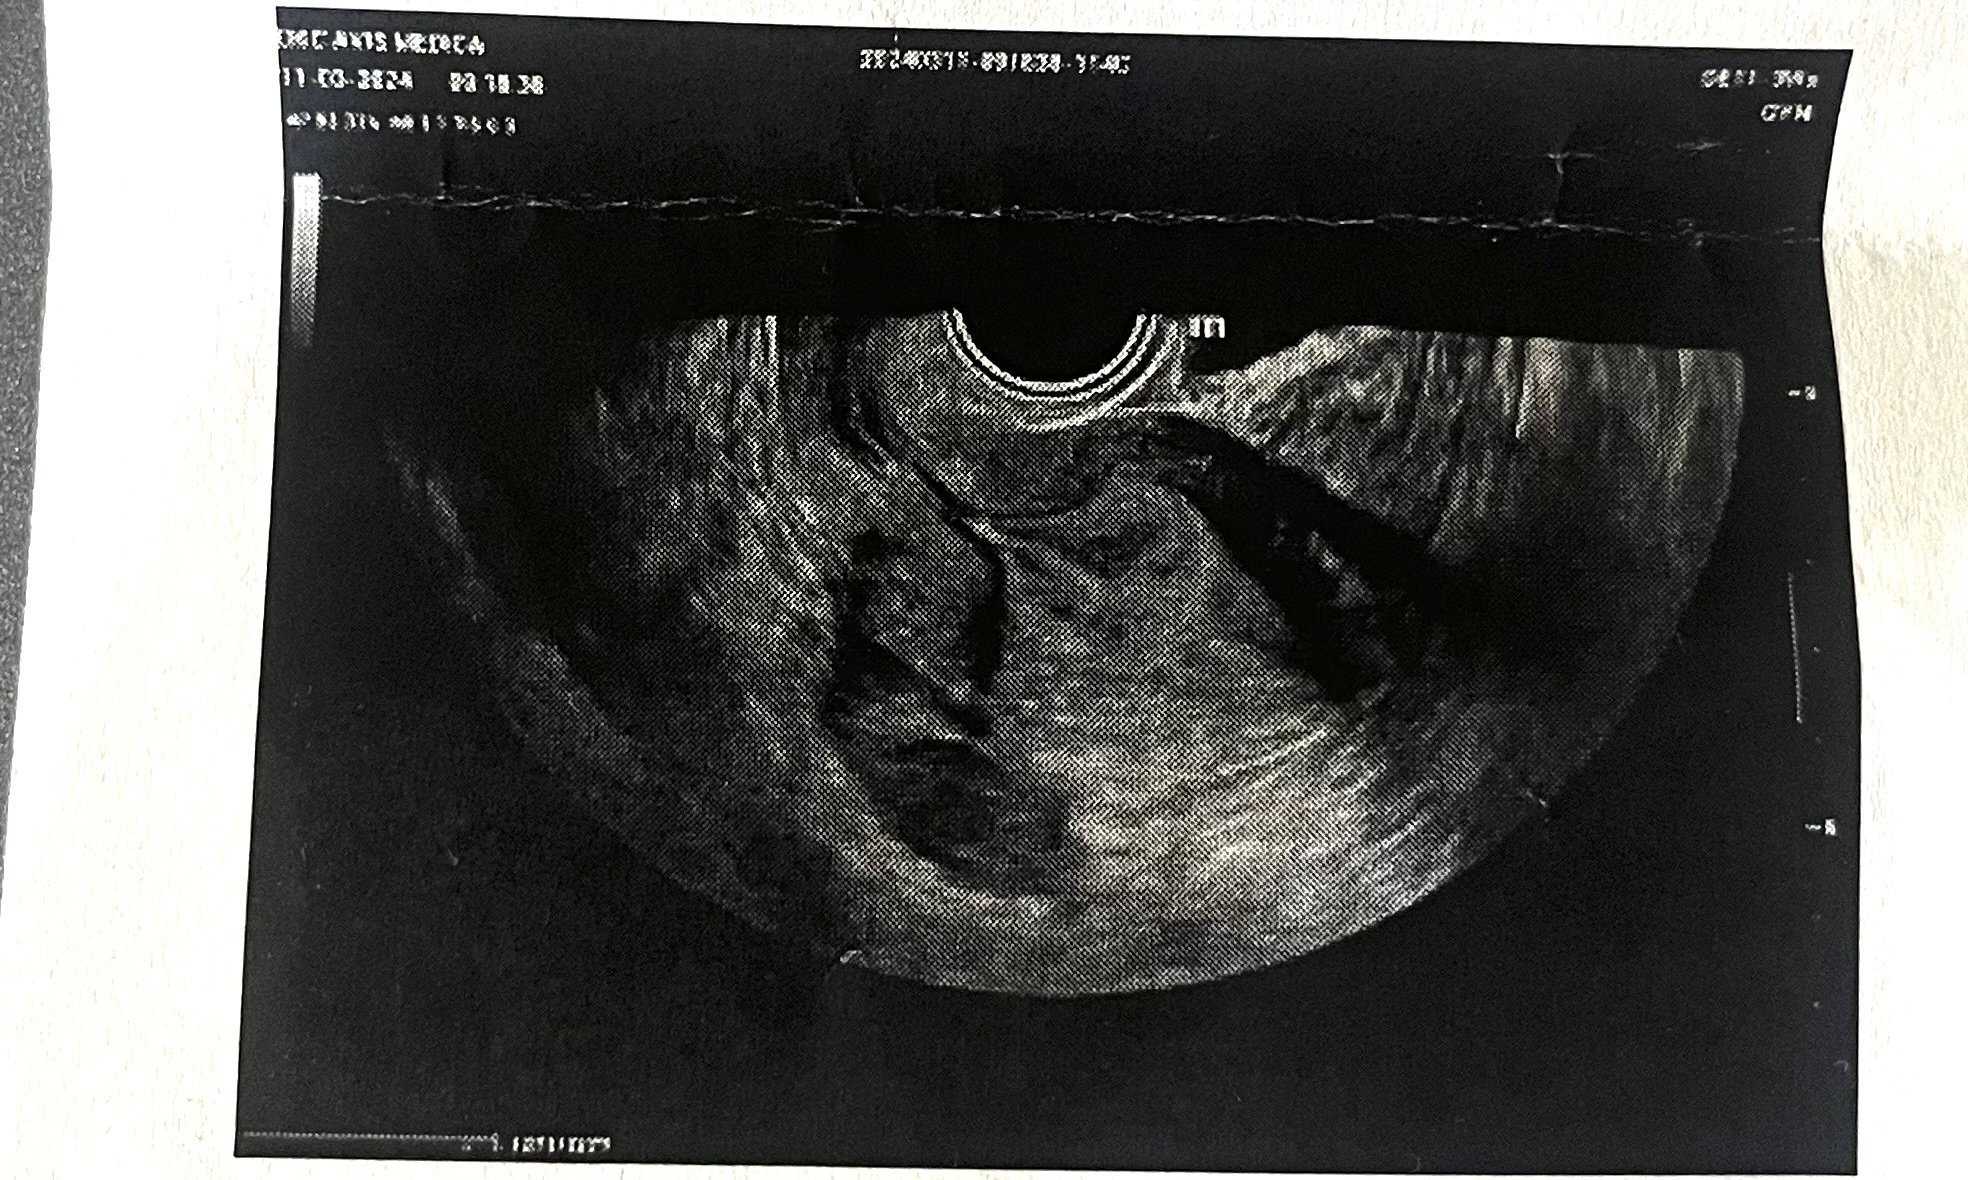

Според вас вижда ли се нещо,това е ехограф 8 дни след закъснението. АГ ми каза,че е рано и не вижда нищо. Другата седмица ще ходя отново. ЧХГ в деня на ехографа беше около 1000.

Диагнозата е D.AMENORRHOEA SECUNDARIA. OBS.GRAVIDITAS(какво означава)

Диагнозата е вторична аменорея (липса на цикъл), с подозрение за бременност. Повечето АГ предпочитат да се отиде към 6-7г.с., за да се види и сърдечна дейност. Успех!

В деня да прегледа бях с ЧХГ около 1000 , АГ каза че не вижда абсолютно нищо за сега,вероятна късна овулация или извънматочна 😱 ЧХГ нараства двойно на 48ч. Надявам се другата седмица да се види.

Щом се е удвойла стойността на ЧХГ е добър знак. Не знам как стой по отношение на извънматочна бременност. Но след седмица като ви викат на преглед трябва да се установи вече със сигурност. Стискам палци да сте отишли просто по-рано!

Мисля, че ако е извънматочна ще се види веднага. То или е в матката, или не е. Не съм доктор, но това не е ли елементарно да се види къде точно е бременността, независимо, че е рано? Вече за ембрион и пулс е друго и трябва поне в 6-7ма седмица да се отиде.

Много е рано да се види нещо на 8ми ден, без значение колко е чхг. Щом е нарастнало правилно значи всичко е наред за момента, бъдете спокойна и изчакайте още седмица. Честито!

При извънматочна бременност чгх не се удвоява